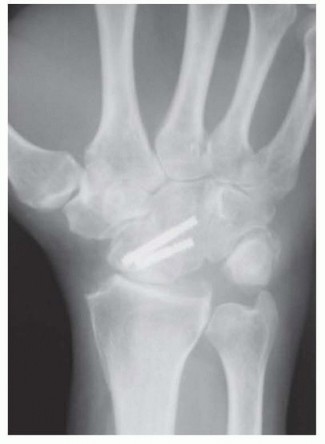

TECH FIG 5 • Scaphocapitate fusion construct using two headless, cannulated compression screws. Note the addition of a radial styloidectomy. (Fingers are at top.)